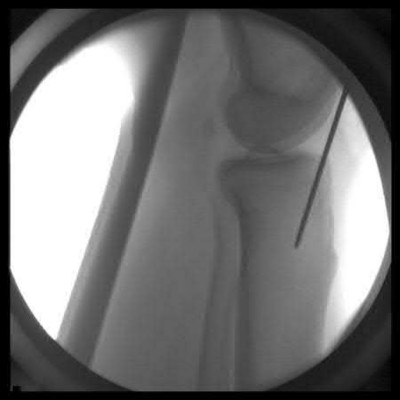

1. # A 32-year-old male sustains the injury shown in Figure A and undergoes treatment as shown in Figure B. Following placement of this implant, what is the best technique to confirm it is not too proud proximally?

1. Lateral radiograph of the knee

The safe zone for tibial nail placement as seen on radiographs is just medial to the lateral tibial spine on the anteroposterior radiograph and immediately adjacent and anterior to the articular surface as visualized on the lateral radiograph.

Tornetta et al specifically located the safe zone for nail entry in a study using fresh frozen cadaver knees. The authors found that the safe zone for nail placement is located 9.1+/-5 millimeters lateral to the midline of the plateau and three millimeters lateral to the center of the tibial tubercle. The width of the safe zone averaged 22.9 millimeters and was as narrow as 12.6 millimeters.

The starting point of the of the nail can be best viewed on the lateral knee radiograph, an example of which is shown in Illustration A. Illustration B shows the "sweet spot" for nail insertion as defined by Tornetta.